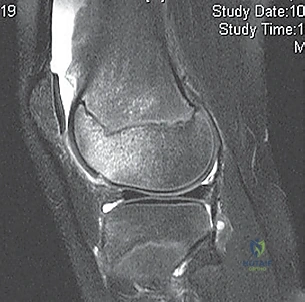

- MRI Scan: Highly recommended for all patients with a large traumatic effusion due to the high rate of occult articular or osteoarticular injury.

* Osteochondral Lesions: Crucial for determining size, location, and potential for repair versus removal.

* Bone Bruise Pattern: Confirms patellar dislocation (medial patella and lateral femoral condyle).

* Anatomical Risk Factors: Assesses patella alta, trochlear dysplasia, tibial tubercle-trochlear groove (TT-TG) distance.

* Bone Bruises: MRI often reveals increased signal on the medial patella and the midportion of the lateral femoral condyle. This distinct pattern helps differentiate it from ACL tears.